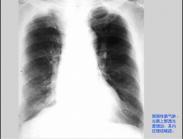

老年人肺氣腫癥狀

• 老年人肺氣腫

628健康網(wǎng)為您分享有關老年人肺氣腫的癥狀,老年人肺氣腫的治療方法,老年人肺氣腫的預防知識,老年人肺氣腫的癥狀圖片,老...